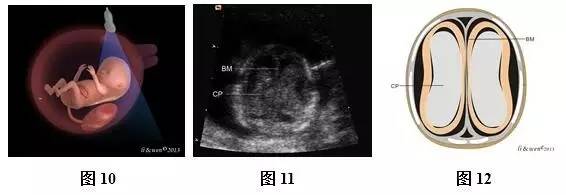

超声扫查方法:声束平面从胎儿前额进入,通过胎儿侧脑室对胎儿颅脑进行横切面扫查(图10),即可获得侧脑室水平横切面(图11,12);然后声束平面以前额为基点,向胎儿尾侧和前方扫查(图13,16,19,22),依次可获得小脑水平横切面(图14,15)、双眼球冠状切面(图17,18)、鼻后三角冠状切面(图20,21)和鼻唇冠状切面(图23,24)。

标准切面判断标准:(1)侧脑室水平横切面:可观察到强回声的脑中线把两侧大脑半球分开,两侧大脑半球内主要为侧脑室及其内的脉络丛占据,大脑实质仅表现为侧脑室周围薄层低回声带,强回声脉络丛几乎充满两侧侧脑室。(2)小脑横切面:可观察到脑中线、丘脑、小脑、第四脑室及颅后窝池等。(3)双眼球冠状切面:可观察到双眼球、硬腭、下颌骨、双耳等。(4)鼻后三角冠状切面:可观察到两块鼻骨、上颌骨、上牙槽及下颌骨等结构。(5)鼻唇冠状切面:可观察到上唇、下唇及鼻等结构。

注:BM为脑中线;CP为脉络丛;T为丘脑;CB为小脑;CM为颅后窝池;EYES为眼球;EAR为耳;NB为鼻骨;SM为上颌骨;IM为下颌骨;ST为上牙槽;N为鼻;UL为上唇;LL为下唇;CH,小脑半球;CV,小脑蚓部;CP,脉络丛;FV,第4脑室;B,脑干

图10~24胎儿颅脑及颜面扫查方法及超声声像图和模式图。图10侧脑室横切面扫查模式图;图11、12侧脑室横切面声像图及模式图;图13小脑横切面扫查模式图;图14、15小脑横切面声像图及模式图;图16双眼球冠状切面扫查模式图;图17、18双眼球冠状切面声像图及模式图;图19鼻后三角冠状切面扫查模式图;图20、21鼻后三角冠状切面声像图及模式图;图22鼻唇冠状切面扫查模式图;图23、24鼻唇冠状切面声像图

主要观察的解剖结构及内容:侧脑室横切面主要观察脑中线是否存在,左右大脑半球是否对称等。小脑横切面主要观察脑中线是否存在,颅后窝池是否存在等。双眼球冠状切面主要观察双侧眼球是否存在、大小及位置,双耳是否存在,硬腭是否连续完整等。鼻后三角冠状切面主要观察鼻骨是否存在,上牙槽是否连续完整等。鼻唇冠状切面主要观察上唇是否连续完整、鼻的形态等。